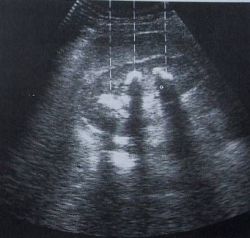

Die Sonographie ermöglicht die Untersuchung

Hierbei können Veränderungen der Organe harmloser Art (z.B. Cysten) aber auch gefährlicher Art (z.B. Bauchaortenaneurysma) festgestellt werden. Ebenfalls kann hierbei sehr sicher beurteilt werden, ob zum Beispiel Gallensteine oder Nierensteine vorhanden sind.